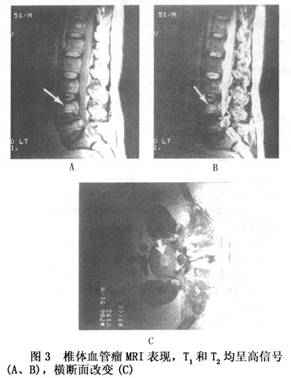

14.4 椎體血管瘤的CT和MRI的表現

CT掃描在診斷椎體血管瘤上具有高度的特異性,病椎呈“火柴束”樣斷面改變(圖2)。與其他骨病變不同的是椎體血管瘤在MRI T1和T2加權像上均呈現信號增強(圖3)。這些斑點的增強的信號與病變的骨的成分相對應,而骨外病竈擴展則在T1加權像不能顯示高強信號。椎體血管瘤運用旋轉回聲技術所進行的MRI檢查,發現病變的不同信號強度很大程度上是由變化的血流速度所決定的,如血管瘤侵入椎管內則CT和MRI均可顯示清楚。